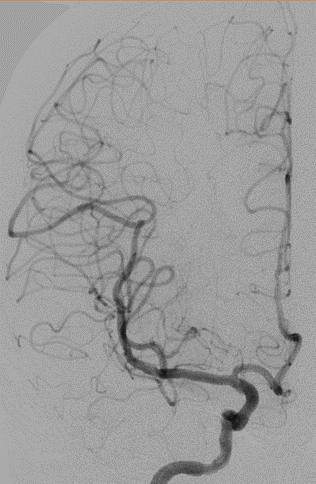

脑血管造影(主动脉弓造影及后循环)

右侧颈动脉造影

左侧颈动脉造影

左侧颈内动脉重建(左侧狭窄及扩张较右侧更甚)

1. 患者双侧颈内动脉多发瘤样扩张及狭窄,其中左侧为甚,破裂出血及出现缺血事件风险较高

2. 拟单枚Surpass Streamline覆盖长段病变